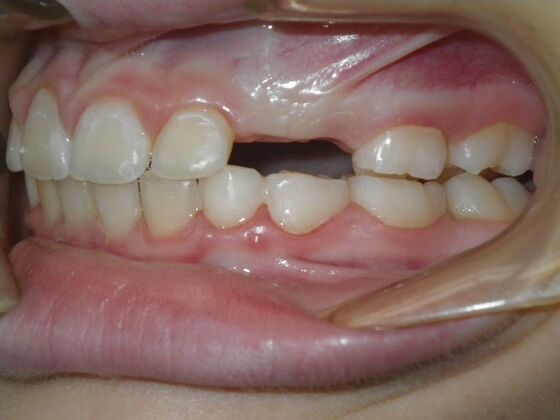

Patient presents with delayed eruption of the upper right central incisor and lower anterior crowding. Treatment plan to include exposure of right central incisor with bracket placement and correction of lower anterior crowding.